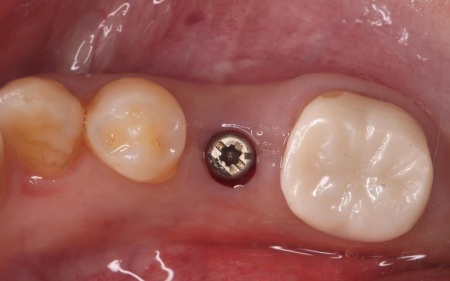

続いてインプラント手術を実施し、インプラントを正しい位置と角度で顎の骨に埋め込みました。

インプラント手術後は経過観察を行い、インプラントが顎の骨に結合したことを確認したら、インプラント上部に取り付ける人工歯を作製するために精密な型取りを実施します。

後日、完成した人工歯をインプラントに装着し、使用感や見た目に問題がないことを確認して、治療を終了しました。